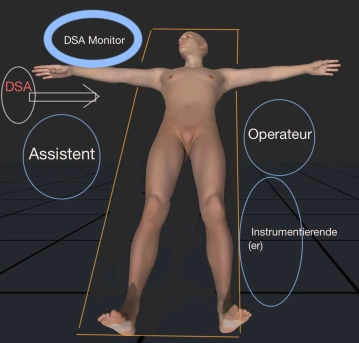

En la contribución se demuestra la exclusión endoluminal de un ulcus ateromatoso penetrante (PAU, excéntrico 32 x 24 mm) de la aorta descendente. Debido a dos operaciones previas de cirugía vascular en la ingle izquierda y arteriosclerosis grave se realiza una exposición extraperitoneal de la A. iliaca externa.